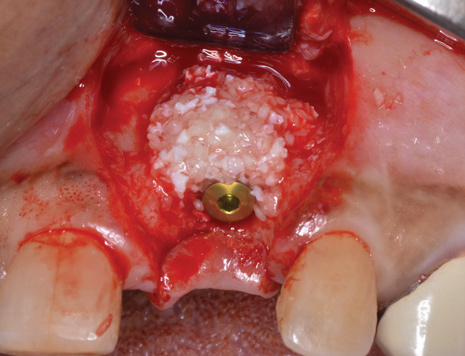

Because the osteotomy created by the trephine is wider than the originally placed implant, it may be challenging to immediately replace this implant unless there is sufficient apical bone available for implant stabilization. For some cases, a wider implant can be placed, but the physiologic rules requiring 1.5 to 2.0 mm for tooth/implant or 3.0 mm for implant/implant spacing,2 as well as other established esthetic criteria, must be respected. For example, a clinical examination revealed a fractured implant in the position of tooth No. 14 along with a fracture to tooth No. 13 (Figure 4). After trephine removal of the fractured implant and extraction of the fractured bicuspid, two implants were placed (Astra Tech, Dentsply Sirona), utilizing apical and axial bone in the apical third of the osteotomy and alveolus to stabilize both fixtures (Figure 5). When this cannot be performed, a staged approach should be employed wherein the site is augmented to facilitate implant placement 4 to 6 months after explantation and grafting.

Occasionally, when a fractured implant is removed via a trephine drill, a wider implant can be placed that will still be within the osseous envelope and respectful of physiologic and esthetic guidelines (Figure 6 through Figure 10). After explantation of an implant with a 3.6-mm diameter body that tapered to 2.5 mm apically, a coronally tapered 4.2-mm diameter implant with a 2.5-mm apical diameter (Astra Tech, Dentsply Sirona) was placed with adequate implant stability. The facial bone lost secondary to the fracture was augmented simultaneously with immediate implant replacement.

(6.) A 3.6-mm diameter implant was removed with a 4.0-mm diameter trephine drill. The apical portion of the implant was luxated carefully to preserve as much bone as possible.

Figure 6

(7.) Because apical and lateral bone volume was preserved with use of an ultrathin trephine, a wider diameter, 4.2-mm implant was placed at the time of implant removal. Bone augmentation was performed, and submerged healing was selected.

Figure 7